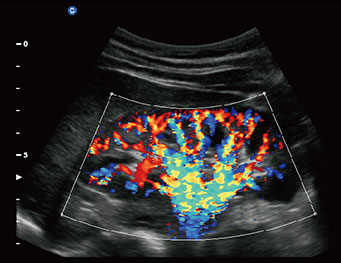

Kidney, C Mode